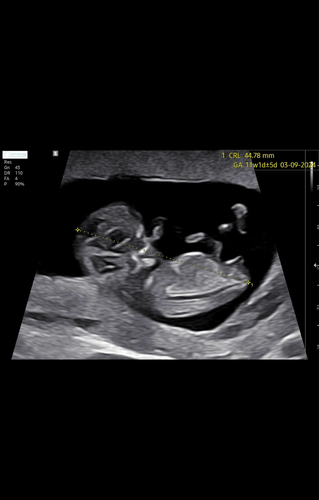

Hoi allemaal! Ik het een vraag over de nub. Ik had een scherpe 11 weken echo en dacht een duidelijke meisjes nub te zien. Is dat dan niet al vrij betrouwbaar? Of is het echt zo dat vaak nog de nub omhoog gaat na 12 weken?

Kan nog omhoog gaan rond die termijn daarom nog niet betrouwbaar helaas 🤍

nee tot 12-13 weken zijn alle baby's nog vrouwelijk. pas tegen die termijn gaan de geslachten zich ontwikkelen 🙂